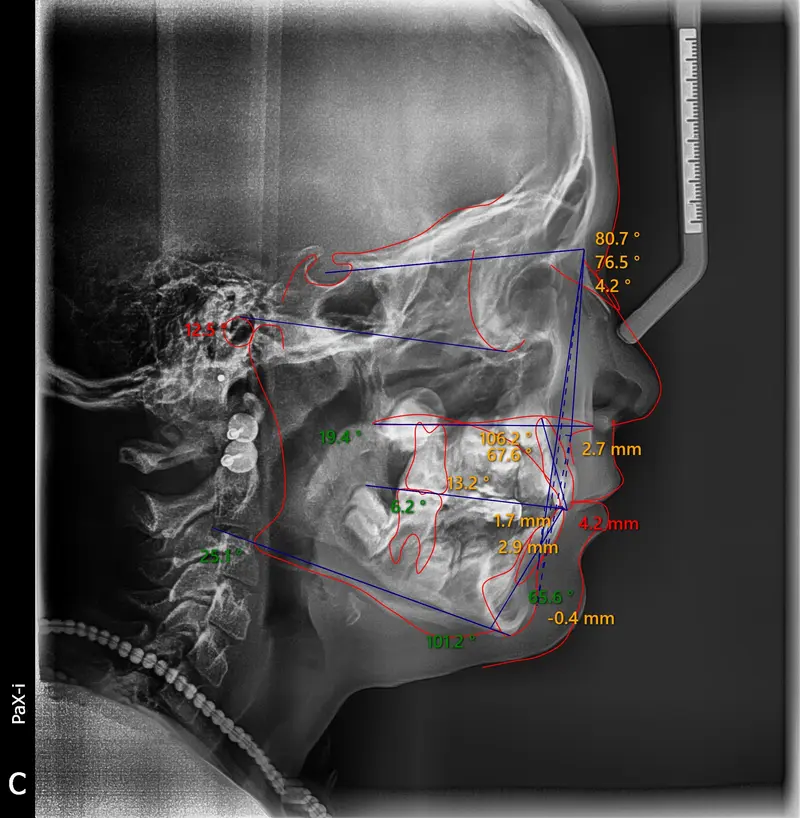

Skeletal Correction 22 Months

The Diagnosis

Bimaxillary protrusion (teeth flaring forward) causing lip incompetence. The patient struggled to close his lips comfortably, straining the chin muscle (mentalis).

The Engineering

A strategic extraction plan (4 premolars) allowed us to retract the front teeth. Note the dramatic improvement in chin projection and facial balance. The extractions did not flatten the face; they harmonized it.